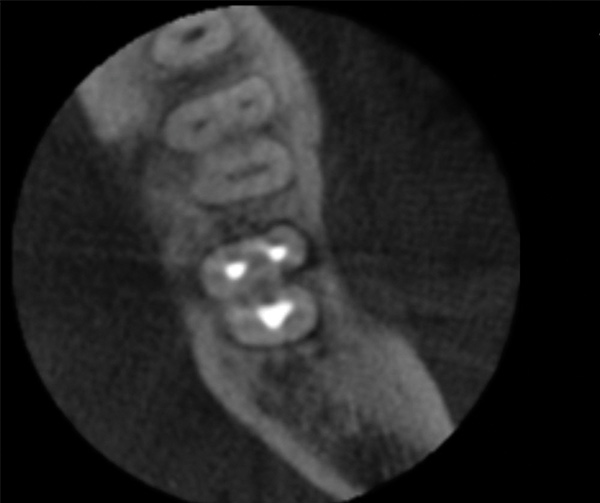

CBCT can be used to aid in further assessment of a previously endodontically treated tooth. A study by Uraba et al demonstrated that CBCT imaging is 20% more effective in detecting periapical lesions that cannot be detected on a periapical radiograph (Figure 1 and Figure 2).7 Diagnostic CBCT can provide additional information in comparison to periapical radiographs when treatment planning an endodontic retreatment case.8 The use of a limited field of view (FOV) CBCT on a patient that presents with a problem on an existing endodontically treated tooth can allow the clinician to critically evaluate the quality of the existing canal(s) obturation, identify any missed canals, and assess the extensiveness of a periapical lesion.

Periapical radiograph of tooth N o. 14 does not definitively reveal

a periapical radiolucency.

Fig 1.

CBCT of the same tooth N o. 14 (palatal

view exposure) shown in Fig 1 definitively shows a periapical lesion.

Fig 2.